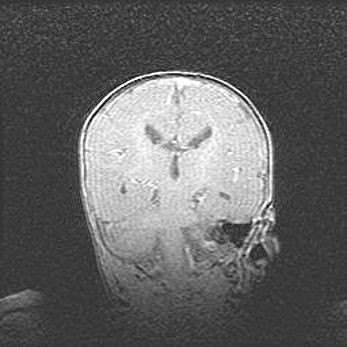

Сообщающаяся гидроцефалия. Кистозная энцефаломаляция головного мозга.

Возраст: 3 месяца 4 дня

Вес: 3100 г

Пол: женский

Окружность головы: 34 см

Срок гестации: 31 неделя

Кистозная энцефаломаляция головного мозга - одна из форм поражения головного мозга в детском возрасте. Характеризуется возникновением множественных и распространённых кист в коре, белом веществе и подкорковых образованиях головного мозга у плодов, новорождённых и детей раннего возраста. Развитие кистозной энцефаломаляции связано с внутриутробной асфиксией и гипотонией, родовой травмой, тромбозом синусов, пороками развития сосудов, инфекциями, сепсисом и другими причинами. Наиболее значимые инфекционные агенты: вирусы простого герпеса, цитомегалии, краснухи, токсоплазмы, энтеробактерии, золотистый стафилококк и другие.